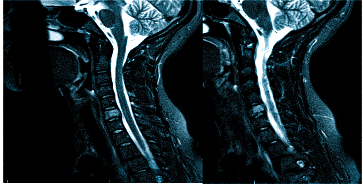

Если оно не дает необходимой картины по проблеме, то может быть назначена , а также: МРТ шейного отдела позвоночника

Важно! Если даже после подобной процедуры не станет ясна причина боли в голове, то потребуется дополнительная диагностика в виде МРТ, но уже позвоночника тела человека, а именно его шейного отдела.